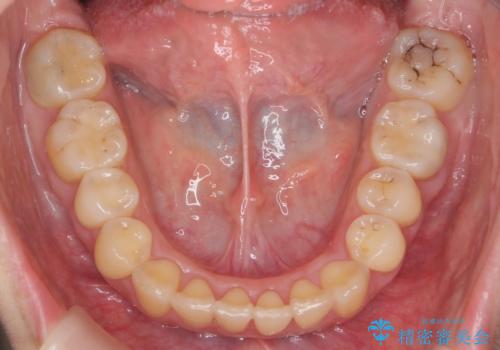

- 20代女性

- インビザライン

- 1年11ヶ月

- 前歯の突出を主訴に来院。

上の奥歯を後ろに下げて治療をしました。

矯正用のミニスクリューを使用しています。

上の前歯もIPR(エナメル質をわずかに削る処置)を行っています。